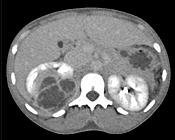

问题 女,32岁,右腰部疼痛伴高热,请根据所示图像,选择最可能诊断 ( )

选项 A、右肾囊肿合并感染 B、右侧急性肾盂肾炎 C、右肾结核 D、右肾脓肿 E、右肾囊性肾癌

答案 D